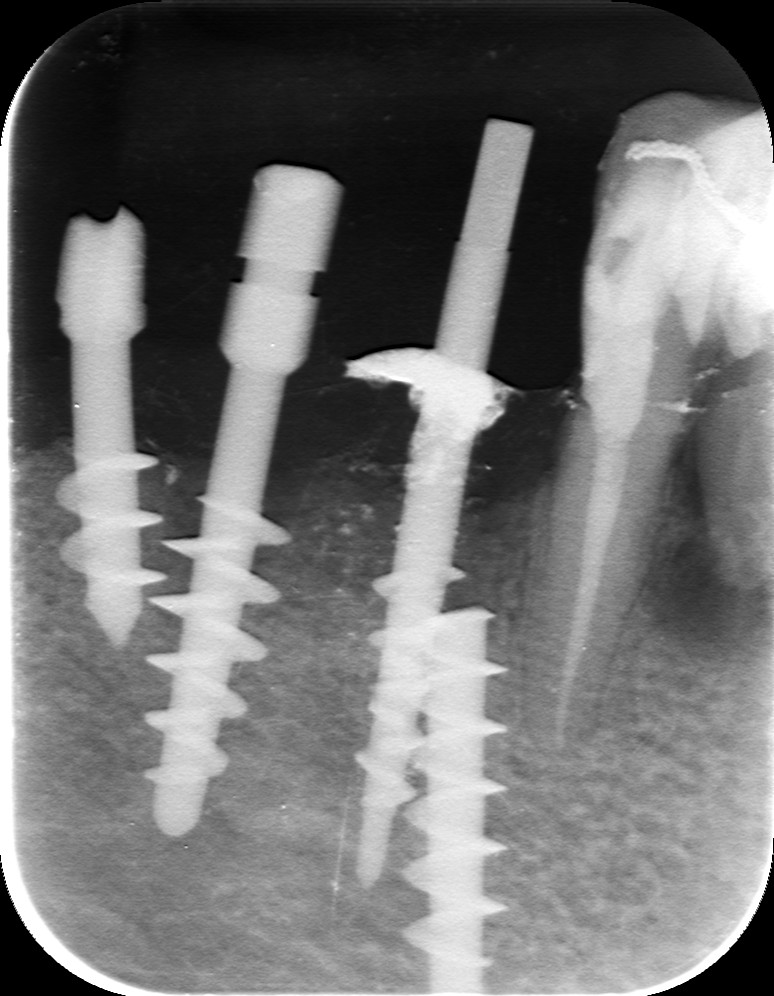

Nella radiografia seguente

si notano: in 6- e -6 due impianti di Tramonte risalenti a circa 40 anni fa (il paz. ne ha perso il ricordo esatto), in -7 un impianto Tramonte "crociante" (si dicono crocianti gli impianti che incrociano il NAI per linguale o per vestibolare), e infine, il problema, un impianto spezzato in posizione 4-. In posizione 65- residua una vecchia protesi in oro e resina, probabilmente risalente all'epoca dell'inserimento implantare, il cui rivestimento estetico è completamente scomparso insieme alla corona di 5-. Il paziente, che ha 81 anni e soffre di una grave forma tumorale, vorrebbe evitare di sottoporsi ad un intervento di estrazione del residuo implantare profondamente infisso in 4- ma patisce l'inefficienza masticatoria di destra e vuole essere riabilitato.Si opta, dunque, per un inserimento appena distale, ma con un piccolo trucco per evitare l'eccessiva distalizzazione del moncone. Il piano di lavoro prevede, dunque, l'estrazione del moncone radicolare in 5- ed un impianto postestrattivo e l'inserimento di un secondo impianto in posizione 4-. Ma in posizione 4- l'inserimento non è possibile, dato il permanere dell'ingombro della porzione endossea dell'impianto fratturato. Si potrebbe inserire distalmente ma così il moncone dell'impianto sostitutivo del 4- verrebbe a trovarsi troppo vicino a quello del postestrattivo in 5-, con conseguenti problemi protesici (spaziatura incongrua) in una zona di un qualche interesse estetico. In questi casi, Garbaccio si rivela la soluzione più efficace semplice e pratica possibile. La sua punta aguzza evita facilmente il residuo fratturato e se anche lo impattasse, gli scivolerebbe di lato trovandosi una strada facilmente con un minimo di guida usando la chiave a cacciavite lunga. Un impianto Tramonte standard non ci riuscirebbe tanto facilmente né in maniera così pulita, ma soprattutto non riuscirebbe a tenersi così accostato poiché si bloccherebbe contro il residuo in inclusione. Poter inserire come si vede in radiografia sfiorando il corpo dell'impianto fratturato, ci permette di ottenere per il moncone una corretta posizione protesica. Il tuttoin maniera facile, semplice, atraumatica, veloce e senza lembo.